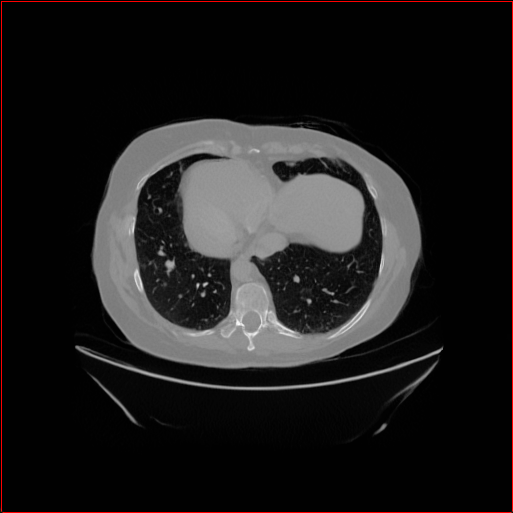

HA-GAN (Sun et al. 2022)

GenerateCT (Hamamci et al. 2024)

MedSyn (Xu et al. 2024)

MAISI-DDPM (Guo et al. 2025)

MAISI-v2

Figure 2: Qualitative comparison across axial (top row), sagittal (middle row), and coronal (bottom row) views. Columns correspond to different methods. MAISI-DDPM and MAISI-v2 in this figure are unconditional synthesis which do not use ControlNet or segmentation maps.

Qualitative Evaluation:

Figure 2 presents representative slices from the axial, sagittal, and coronal planes. GenerateCT (Hamamci et al. 2024) is a 2D model, so it lacks inter-slice consistency, leading to poor image quality in the sagittal and coronal views. MedSyn (Xu et al. 2024) produces noticeably blurry results with mosaic-like artifacts, such as region inside the red box. HA-GAN (Sun et al. 2022) generates visually sharp images but with mosaic-like artifacts, such as region inside the red box. Also, its voxel spacing is not available, which limits its applicability in real-world medical imaging tasks. Moreover, all three methods are restricted to synthesizing small anatomical regions. In contrast, both MAISI and MAISI-v2 are capable of generating high-quality 3D volumes that span larger body regions while preserving fine anatomical details and realistic structure.